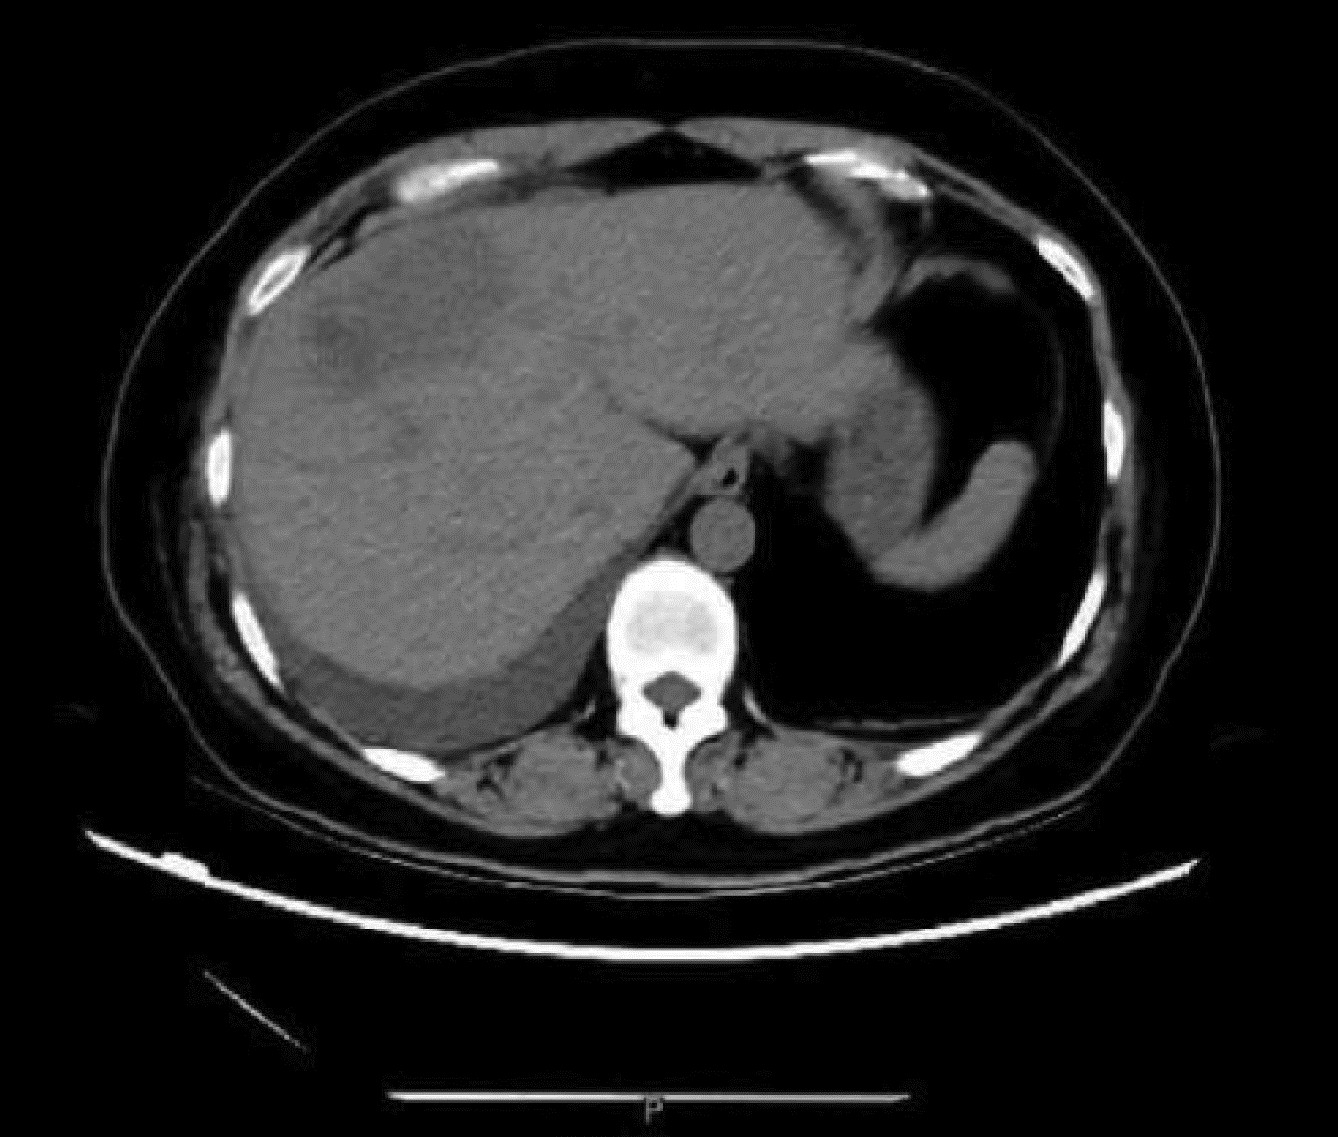

Massive hepatic hemangioma with diffuse arterioportal fistula: A case report

Bangjian ZHOU, Jun YANG, Yu YIN, Xiaoli ZHU, Caifang NI, Wansheng WANG

2023, 39(3): 640-643. DOI: 10.3969/j.issn.1001-5256.2023.03.025

Abstract(977) HTML (223) PDF (3500KB)(99)

Abstract: